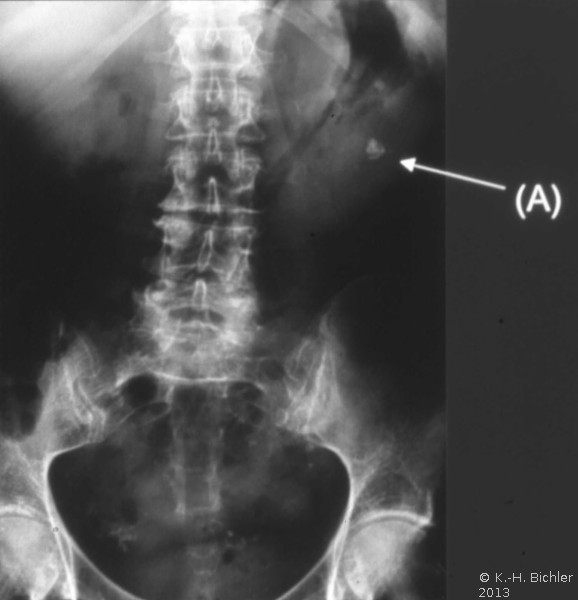

Literatur:http://www.bundesaerztekammer.de/page.asp?his=1.120.121.1042.5974; Leitlinie zur Qualitätssicherung in der Röntgendiagnostik: Qualitätskriterien röntgendiagnostischer Untersuchungen; Bundesärztekammer Stand: 23.11.2007. Sie schreibt das Verwenden von umschließenden Hodenkapseln, Ovarienabdeckungen und Bleigummiabdeckungen für den an das Nutzstrahlenfeld angrenzenden Körperbereich vor (

10 Abbildungen).